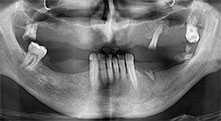

dentatura residua

Un paziente di 40 anni con una dentatura residua limitata desiderava un restauro basato su impianto. Dal momento che è un fumatore, era controindicato un rialzo del seno mascellare con una protesi fissa. È stata quindi programmata una protesi a barre.